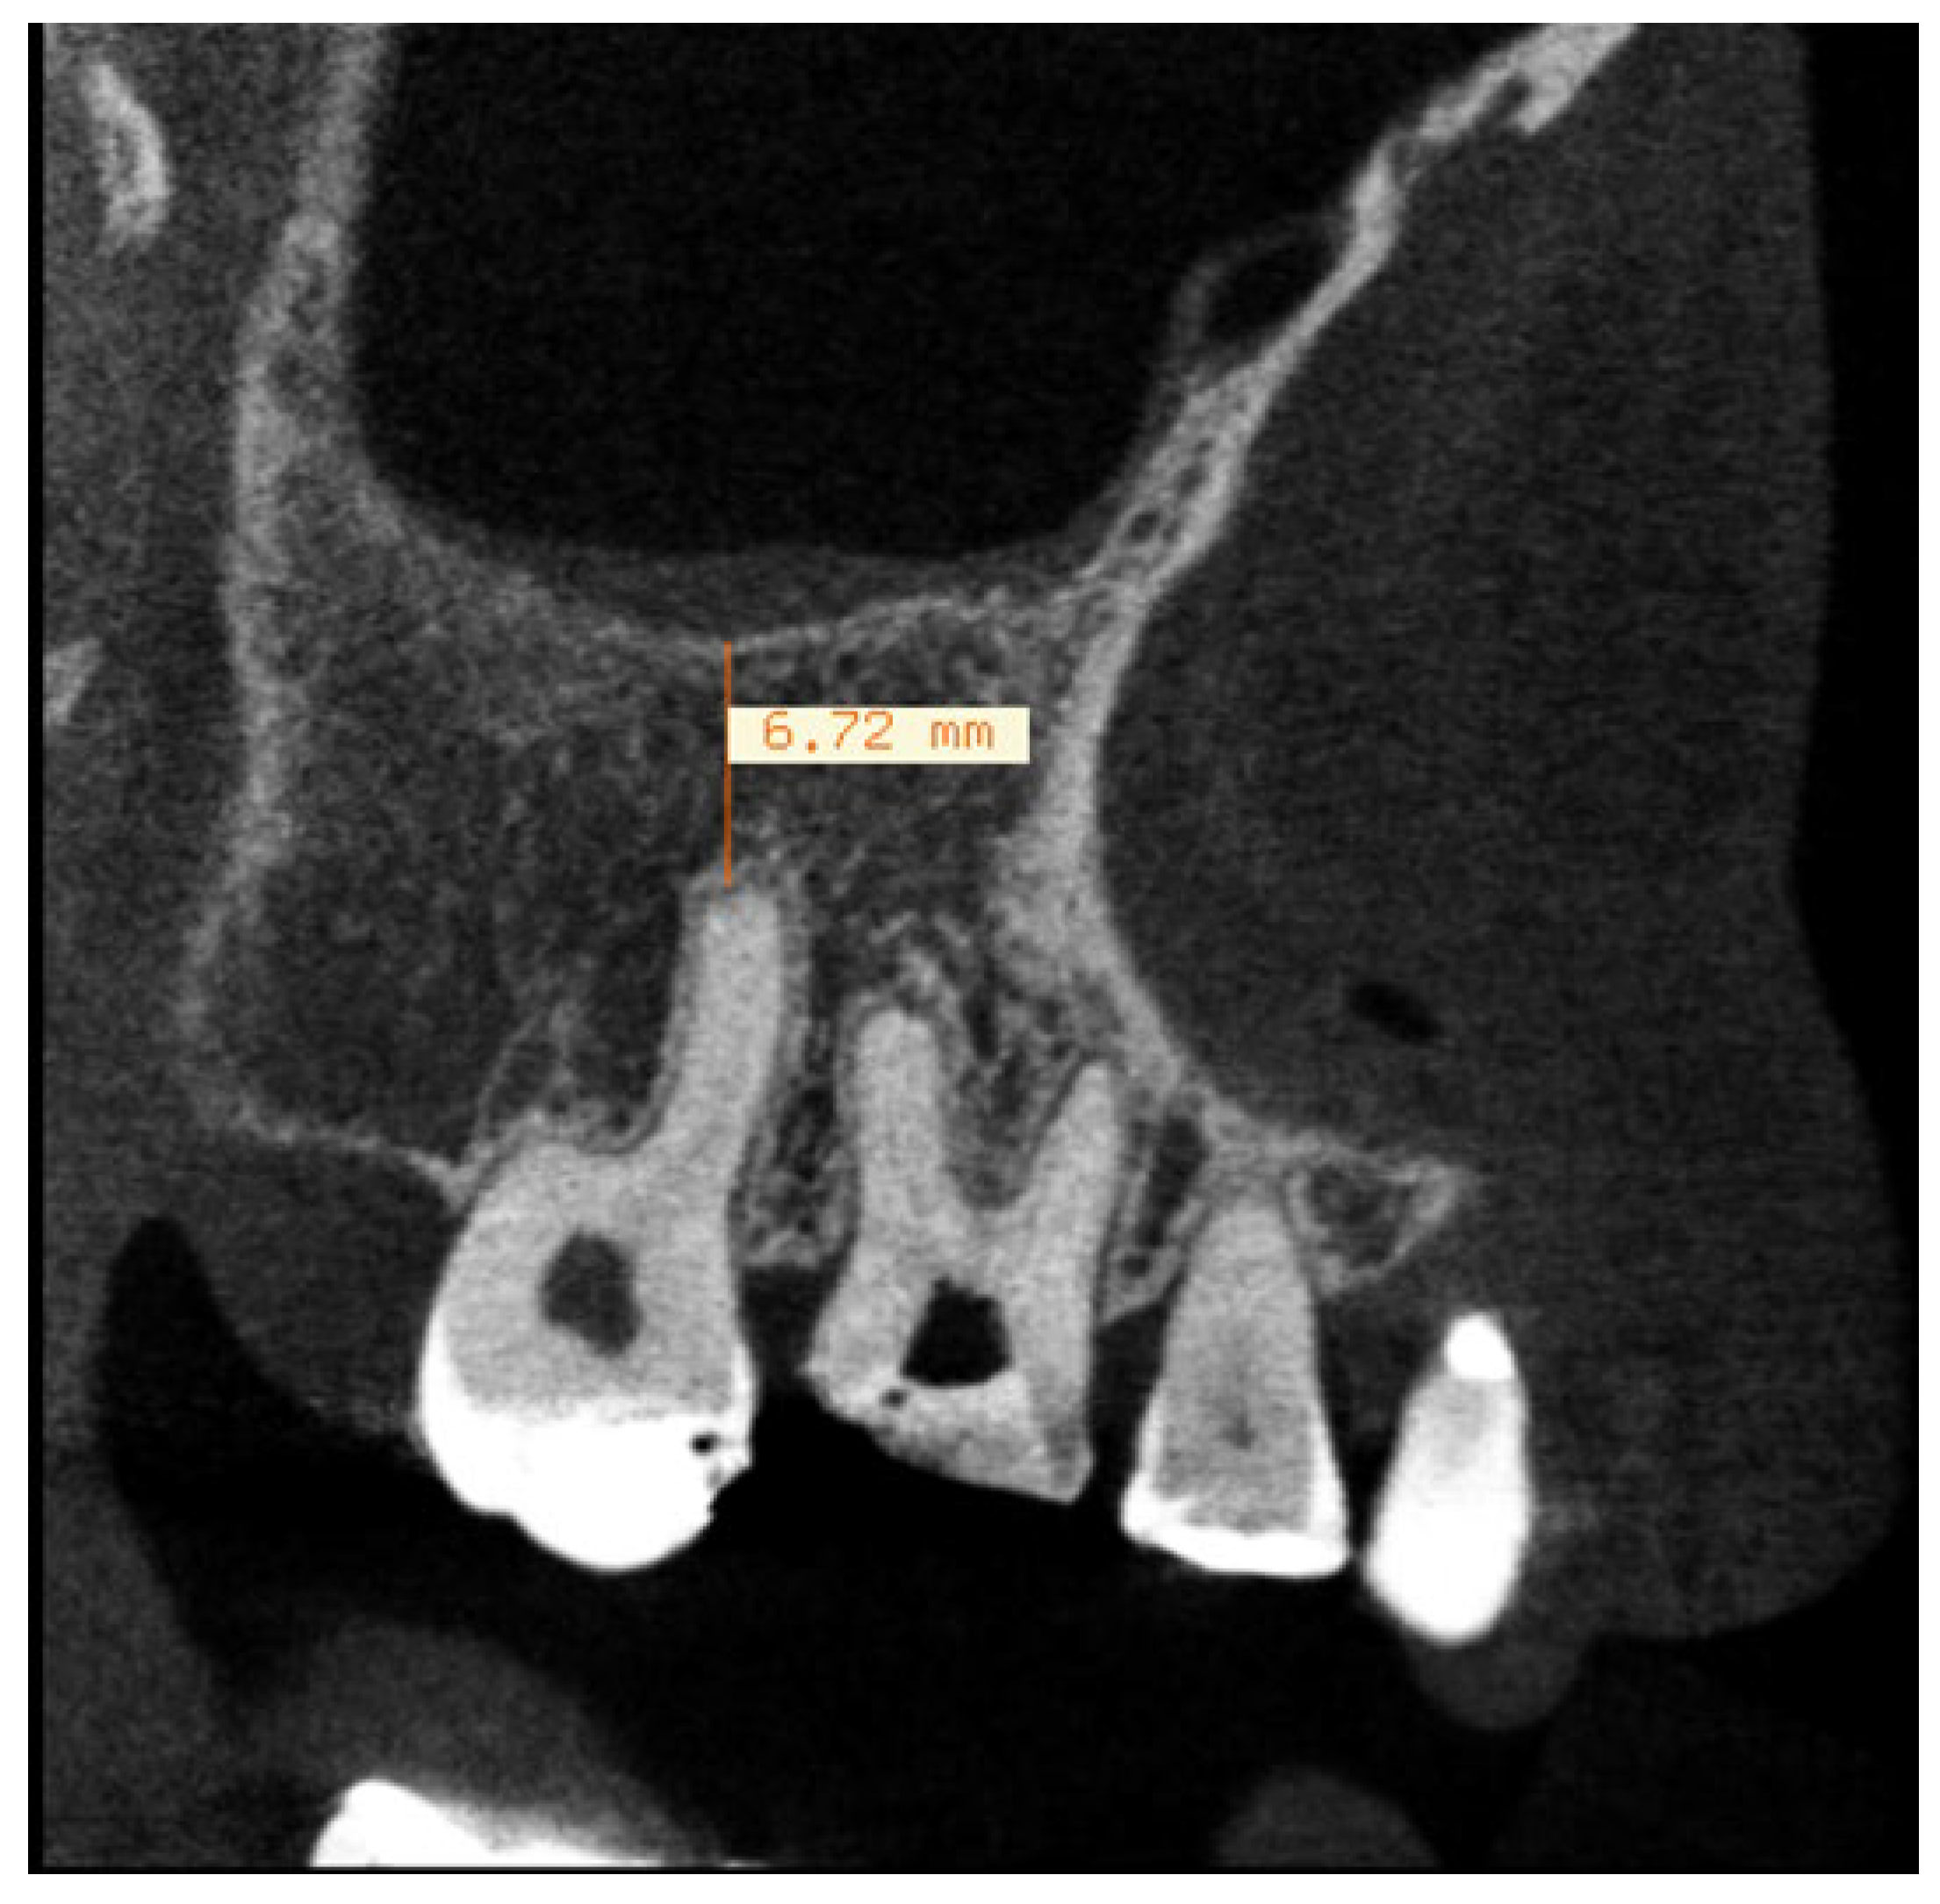

After the whole tomographic volume was analyzed in sagittal and coronal views, the sagittal slice that allowed the clearest visualization of the relationship between the apex and the maxillary sinus floor was selected and the linear distance between the 2 structures measured (Figure 1). The width of the sinus membrane was measured, whenever it was apparent, in the areas immediately adjacent to each tooth. The parameters set by Nurbakhsh et al. (2011) [44], that considered as normal, cases with up to 1mm thick membrane; mucositis when the membrane width was up to 3.54mm; and images suggestive of sinusitis in cases above 3.54mm were used as references to categorize the condition of each membrane studied (Figure 2). Besides that, the maxillary sinus condition was assessed using the LUND-MACKAY SCORE [45], in which, the maxillary sinus can be grouped in 3 categories according to the opacification detected on an image, being 0=completely clean sinus; 1=partial opacification; 2=complete opacification. The Lund-Mackay score was used because it is a simple score, that requires virtually no previous training and is frequently used by Otolaryngologists. [51].

Figure 2. Example of thickened sinus mucosa measured according to the parameters by Nurbakhsh et al. (2011).